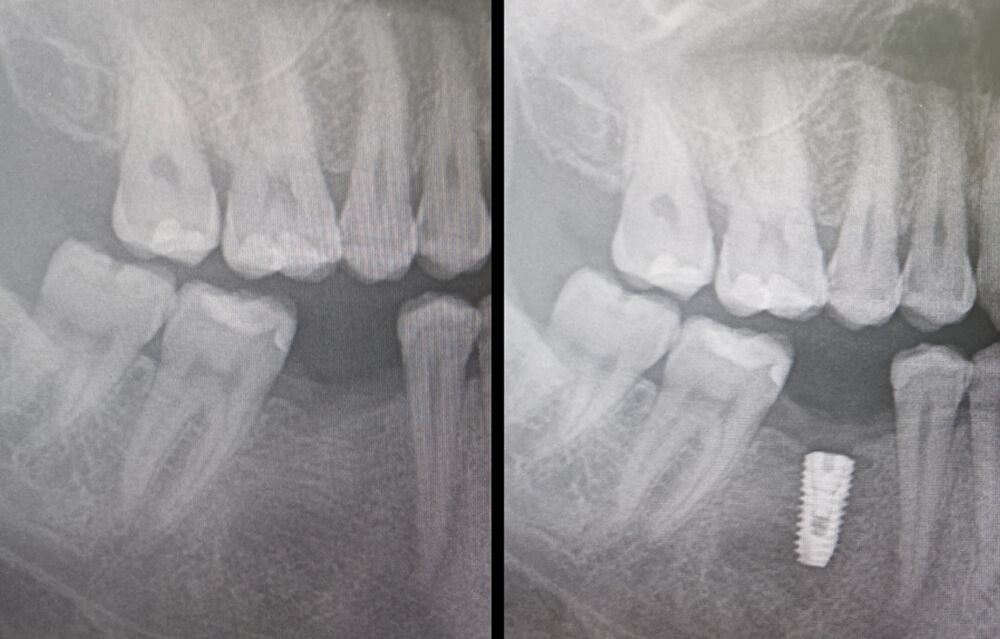

Dental implant; ağızda eksik dişlerin yerine çene kemiği içerisine yerleştirilen, diş kökünü taklit eden titanyum vidalardır. Bu vidaların üzerine yerleştirilen uygun diş protezleri ile eksik dişlerin yeri doldurulur.

İmplant cerrahisi genelde ilgili bölgenin lokal anestezisi ile yapılır ve uygulanacak implant sistemine göre çene kemiğinde yapılması planlanan yerlere özel diriller ile implant boşlukları hazırlanır ve implantlar bu boşluklara yerleştirilir. Uygun koşullarda diş çekiminin yapıldığı sırada hemen implant uygulamaları da yapılabilmektedir.